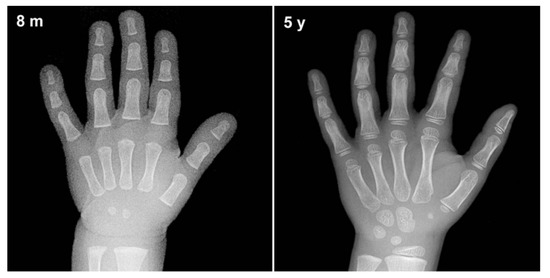

5.1. Dataset